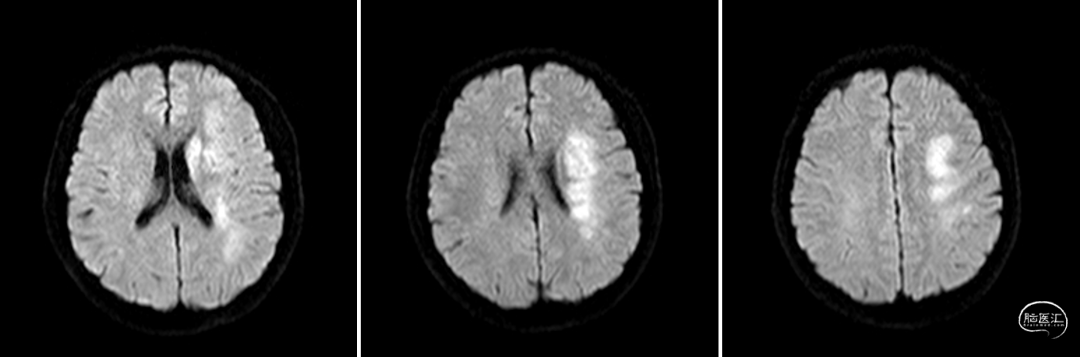

DWI

重要影像结论:左基底节区及放射冠区脑梗死。

术后影像及检查

全脑及病变处不同体位造影:狭窄处成形好,未残余明显狭窄,左大脑中动脉主干及各分支显影好。